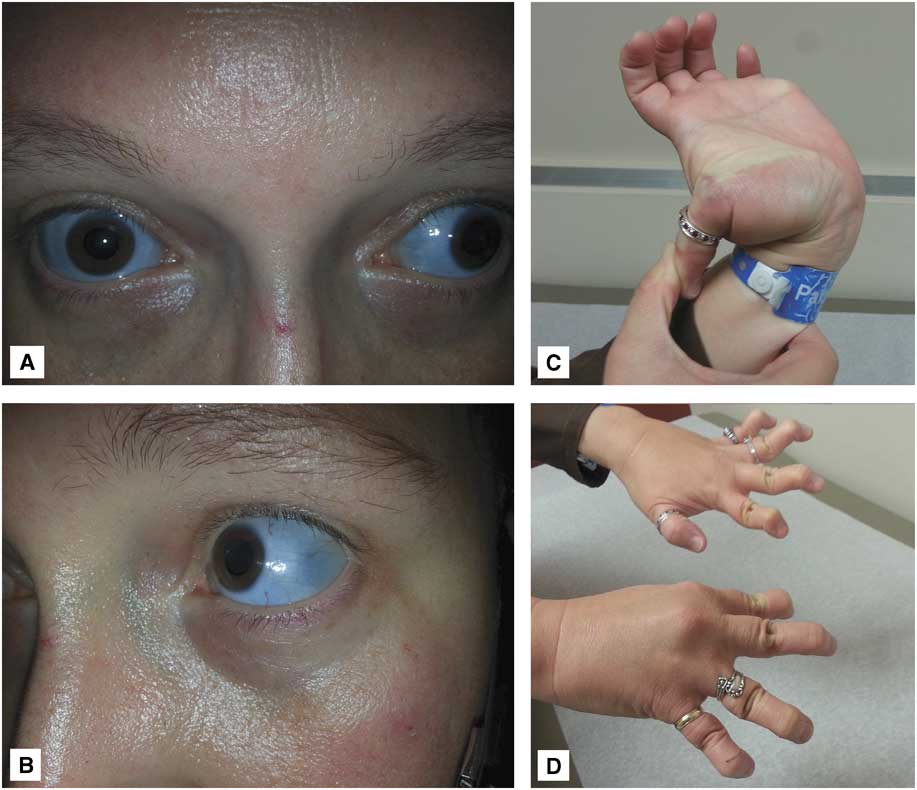

Further questioning of the family revealed that the patient had type I (autosomal dominant) OI, as did roughly 50% of her siblings and children. Interestingly, the patient’s mother had died of aneurysmal SAH and one of her maternal aunts had had surgical clip ligation of an intracranial aneurysm. The patient and one of her daughters exhibited obvious clinical signs of OI, including blue-tinted sclerae, joint hyperlaxity, and finger deformities secondary to multiple prior healed fractures (Figure 2). The patient never smoked tobacco and had no history of hypertension.

Figure 2 Photographs of the patient’s daughter demonstrate typical clinical features of osteogenesis imperfecta: (A, B) blue-tinted sclerae and (C, D) joint hyperlaxity.

The clinical features of OI vary greatly from person to person, even among people with the same type and within the same family. Although the most severe forms may result in death at birth or during infancy, the mildest forms can be associated with a normal life expectancy. Skeletal pathology, including fragile bones and frequent pathologic fractures, is a hallmark of the disease. Likewise, blue sclerae are a characteristic finding and help distinguish OI from other heritable connective tissue disorders. Other manifestations may include fragile skin, easy bruising, muscle weakness, joint laxity, curved bones, short stature, scoliosis, brittle teeth (dentinogenesis imperfecta), hearing loss, and restrictive pulmonary disease.Reference Rauch and Glorieux 7 - 9